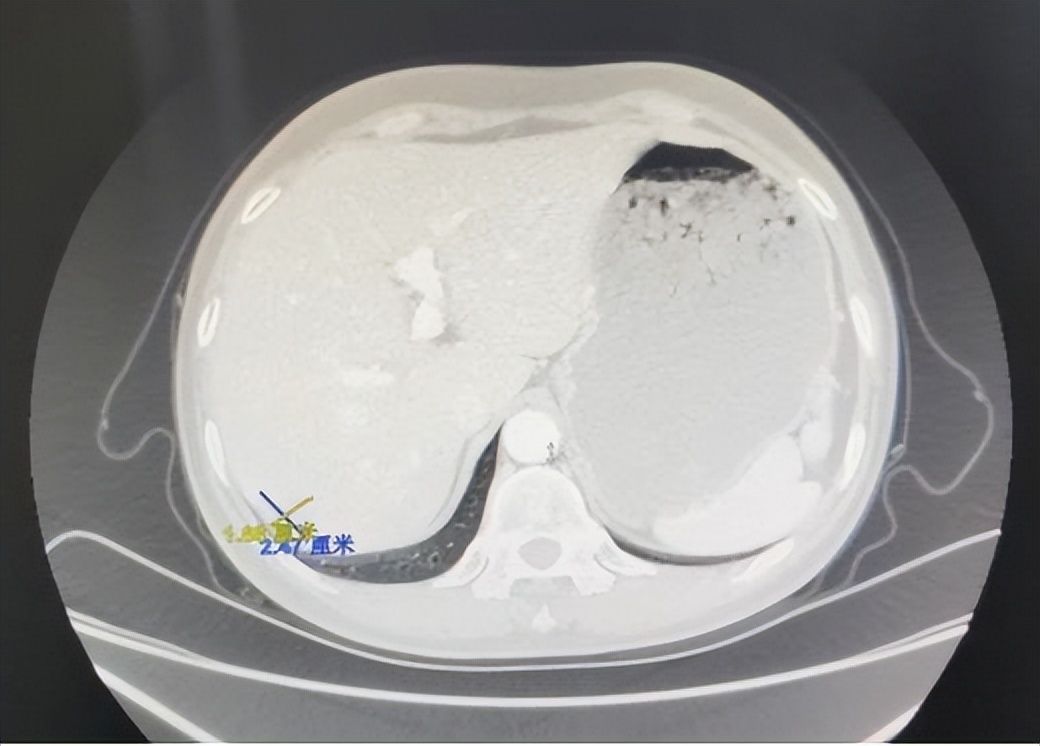

胸腹部CT平扫+增强:与2020-7-29腹部及2020-4-16胸部前片比,肝右叶新增稍低密度影(1.48*1.33cm),转移可能大,建议结合MR;余胸腹部情况基本同前。

2023-04-05复查CT提示:(与2023-02-10 CT比较)肝右叶结节,较前饱满(2.47*1.88cm),考虑转移。腹主动脉左旁及左侧髂血管旁部分淋巴结较前稍饱满。考虑病情进展。